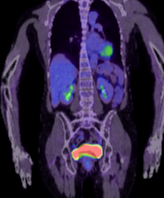

FDG PET/CT

核

医学

FDG摄取阴性

初步报告提示可能存在转移性疾病,因此进行了FDG PET/CT进一步评估。本例结果令人放心;SUV值可能与恶性

肿瘤

重叠。此外,MRI表现多样,病灶在T2加权序列上可呈高信号,并在注射钆后增强。